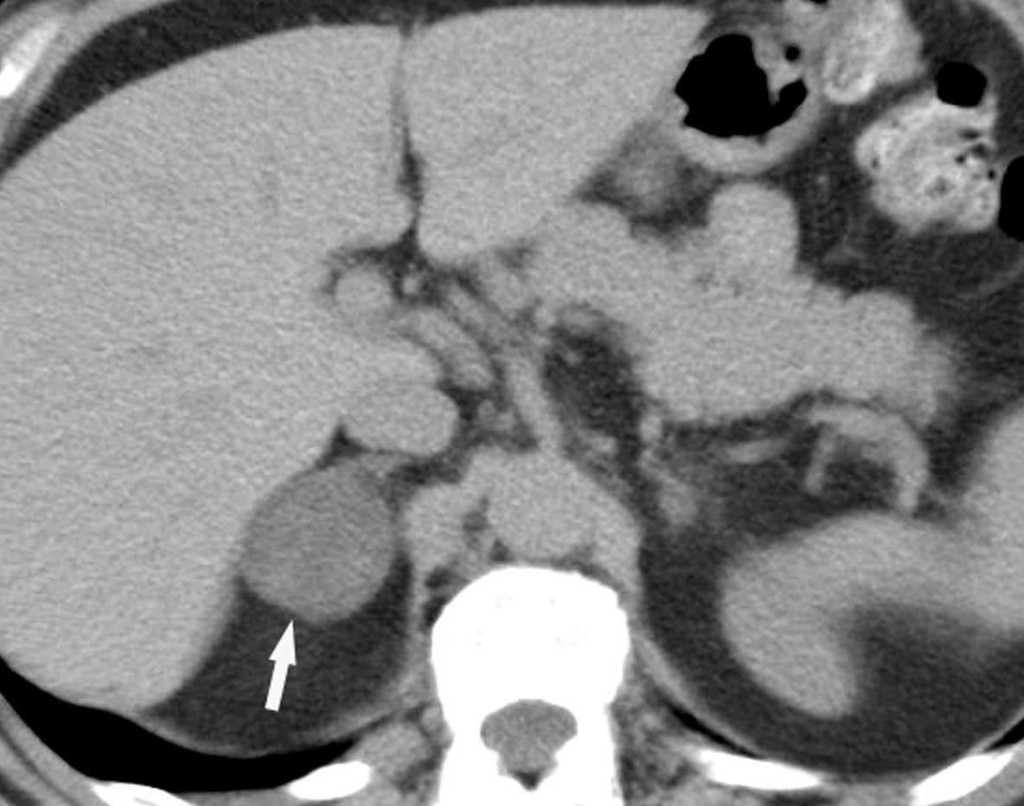

Fig. 11.--N2. (A) Corte axial de tomografía computarizada (TC) con contraste. Nódulo heterogéneo en el segmento 6 del lóbulo inferior derecho con infiltración de la vena pulmonar inferior (flecha). (B) En la reconstrucción de volumen se ponen de manifiesto la infiltración tumoral de la vena pulmonar (flecha negra), la adenopatía hiliar (asterisco) y una adenopatía calcificada lobar superior derecha (flecha blanca).

Fig. 12.--Estaciones ganglionares para la estadificación del cáncer de pulmón. Las reconstrucciones multiplanares (MPR) son de gran ayuda para precisar los territorios ganglionares afectos. Correlación de los territorios ganglionares entre el mapa ganglionar de Mountain y Dressler y una reconstrucción coronal de un paciente con afectación adenopática mediastínica e hiliar bilateral. (A y B) Ganglios mediastínicos superiores e inferiores e hiliares. (C y D) Ganglios aórticos. AP: arteria pulmonar. Ao: aorta.

La precisión de la TC para predecir la afectación ganglionar mediastínica, pese a la ayuda que suponen las reconstrucciones MPR y 3D en la valoración de determinados territorios ganglionares (espacio subcarinal, hilio o ventana aortopulmonar) (fig. 11), sigue teniendo muchas limitaciones. El único criterio que se emplea para considerar que un ganglio es patológico es el tamaño (cuando el eje corto es mayor de 10 mm, salvo en el espacio subcarinal que se acepta hasta 12 mm). El empleo únicamente de criterios de tamaño hace que la TC sea una técnica poco precisa en la valoración de la afectación ganglionar. En un metaanálisis reciente13 la sensibilidad global de la TC para estadificar el mediastino fue de un 57%, con una especificidad del 82%, un valor predictivo positivo (VPP) del 56% y un valor predictivo negativo (VPN) del 83%. Lo que es innegable es la capacidad de la TC para mostrar un mapa de los ganglios tanto hiliares como mediastínicos (fig. 12), lo cual es de gran utilidad en la determinación del factor N. La valoración del territorio hiliar puede ser compleja por la agrupación de estructuras vasculares, por lo que además de la opacificación adecuada de éstas, es de utilidad la identificación de la pérdida del ángulo de la bifurcación (carina secundaria), ya que el eje corto significativo en este territorio es de 3 mm. Como ya hemos comentado, también es de gran ayuda en esta localización el empleo de reconstrucciones (fig. 11)5.